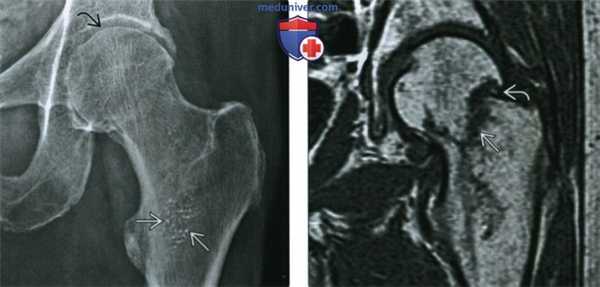

(Слева) Рентгенография в ПЗ проекции: определяются характерные признаки остеопении. Обратите внимание на истончение компактного вещества головки бедренной кости. Несмотря на диффузное истончение трабекул, в определенных стрессовых участках они могут оставаться не измененными и противостоять нагрузкам в пораженной остеопорозом кости, как видно в данном случае, где имеются крупные первичные трабекулы.

(Справа) На фронтальной Т1ВИ МР-томограмме определяется субкапитальный перелом бедренной кости. Согласно одной из теорий, стрессовые переломы бедренной кости, возникающие в верхнелатеральном отделе, прогрессируют до полного, что приводит к падению, а не падение приводит к перелому.